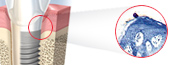

1. DENTAL IMPLANTS

We can give you teeth that don't move when you speak or chew!

EASY ESTHETICS SOFT TISSUE INTEGRATION IMMEDIATE FUNCTION

We are using the following dental implants routinely at Dr. Cheemas multispeciality implant centre.

A.TiUnite®

uniquely effective implant surface provides optimal conditions for Soft Tissue Integration™ and  osseointegration.

B.Groovy

Groovy, completely new and unique groove system, takes all our implants to a higher level of effectiveness.

With research showing that bone loves bonding with grooves, extended to the collar of most new implants so they:

- Increase surface area

- Increase area for bone-to-implant contact

C.Immediate Function™

This concept makes it possible for patients to leave the dentist directly after implant placement with

their new teeth in place – ready to eat, drink and smile.